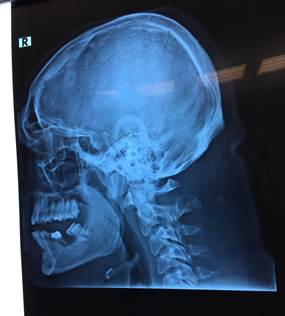

Діагностика акромегалії.